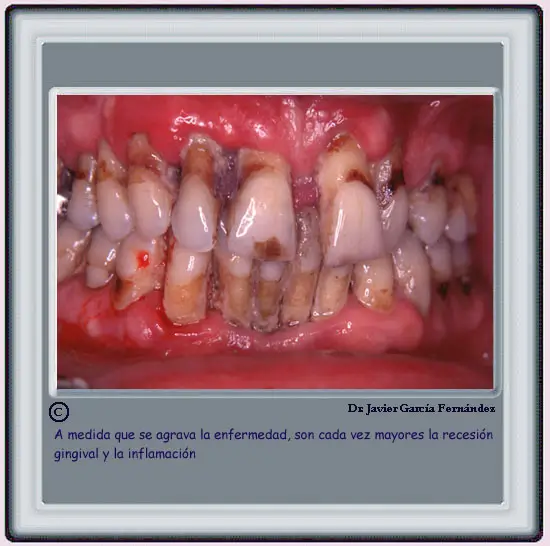

De la Salud a la Enfermedad Periodontal

Página anterior Agravamiento de la enfermedad Página siguiente